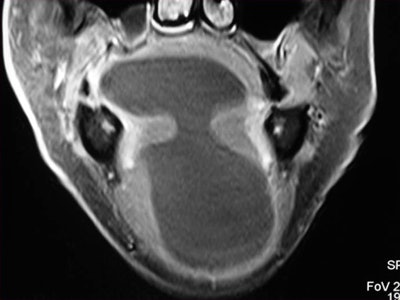

Axial T2-weighted MR image through the floor of the mouth shows a small squamous cell carcinoma (SCC) strategically located in the anterior floor of the mouth. The SCC is obstructing the draining ducts of the sublingual gland with an associated plunging ranula. Image courtesy of Dr. Alexandra Borges.Referring to the choice of imaging technique, she highlights the importance of considering different patients' specificities. Heavy smokers and drinkers prone to salivary stasis, difficulty in swallowing, and dyspnea are not good candidates for MRI, as this technique is very prone to motion artifacts, and patients with many dental fillings and/or dental implants may do better with MRI than with CT, she explained.

In terms of technical issues to note when imaging the oral cavity, Borges has plenty of good advice. She points out that dental-related artifacts can be avoided by angling the axial sections parallel to the dental fillings on CT or opting for MRI. When lesions are located in the gingival sulcus, jugal or palatal mucosa, or the tongue, cheek puffing is very helpful to clearly depict the full extent of the lesion and separate the lesion from the adjacent mucosal surfaces, she noted.

Finally, she emphasized that when using MRI, it is crucial to instruct a patient not to swallow and to breathe quietly during the entire examination. The use of surface coils can be very helpful for the imaging of superficially located lesions such as the parotid and submandibular glands and the floor of the mouth.